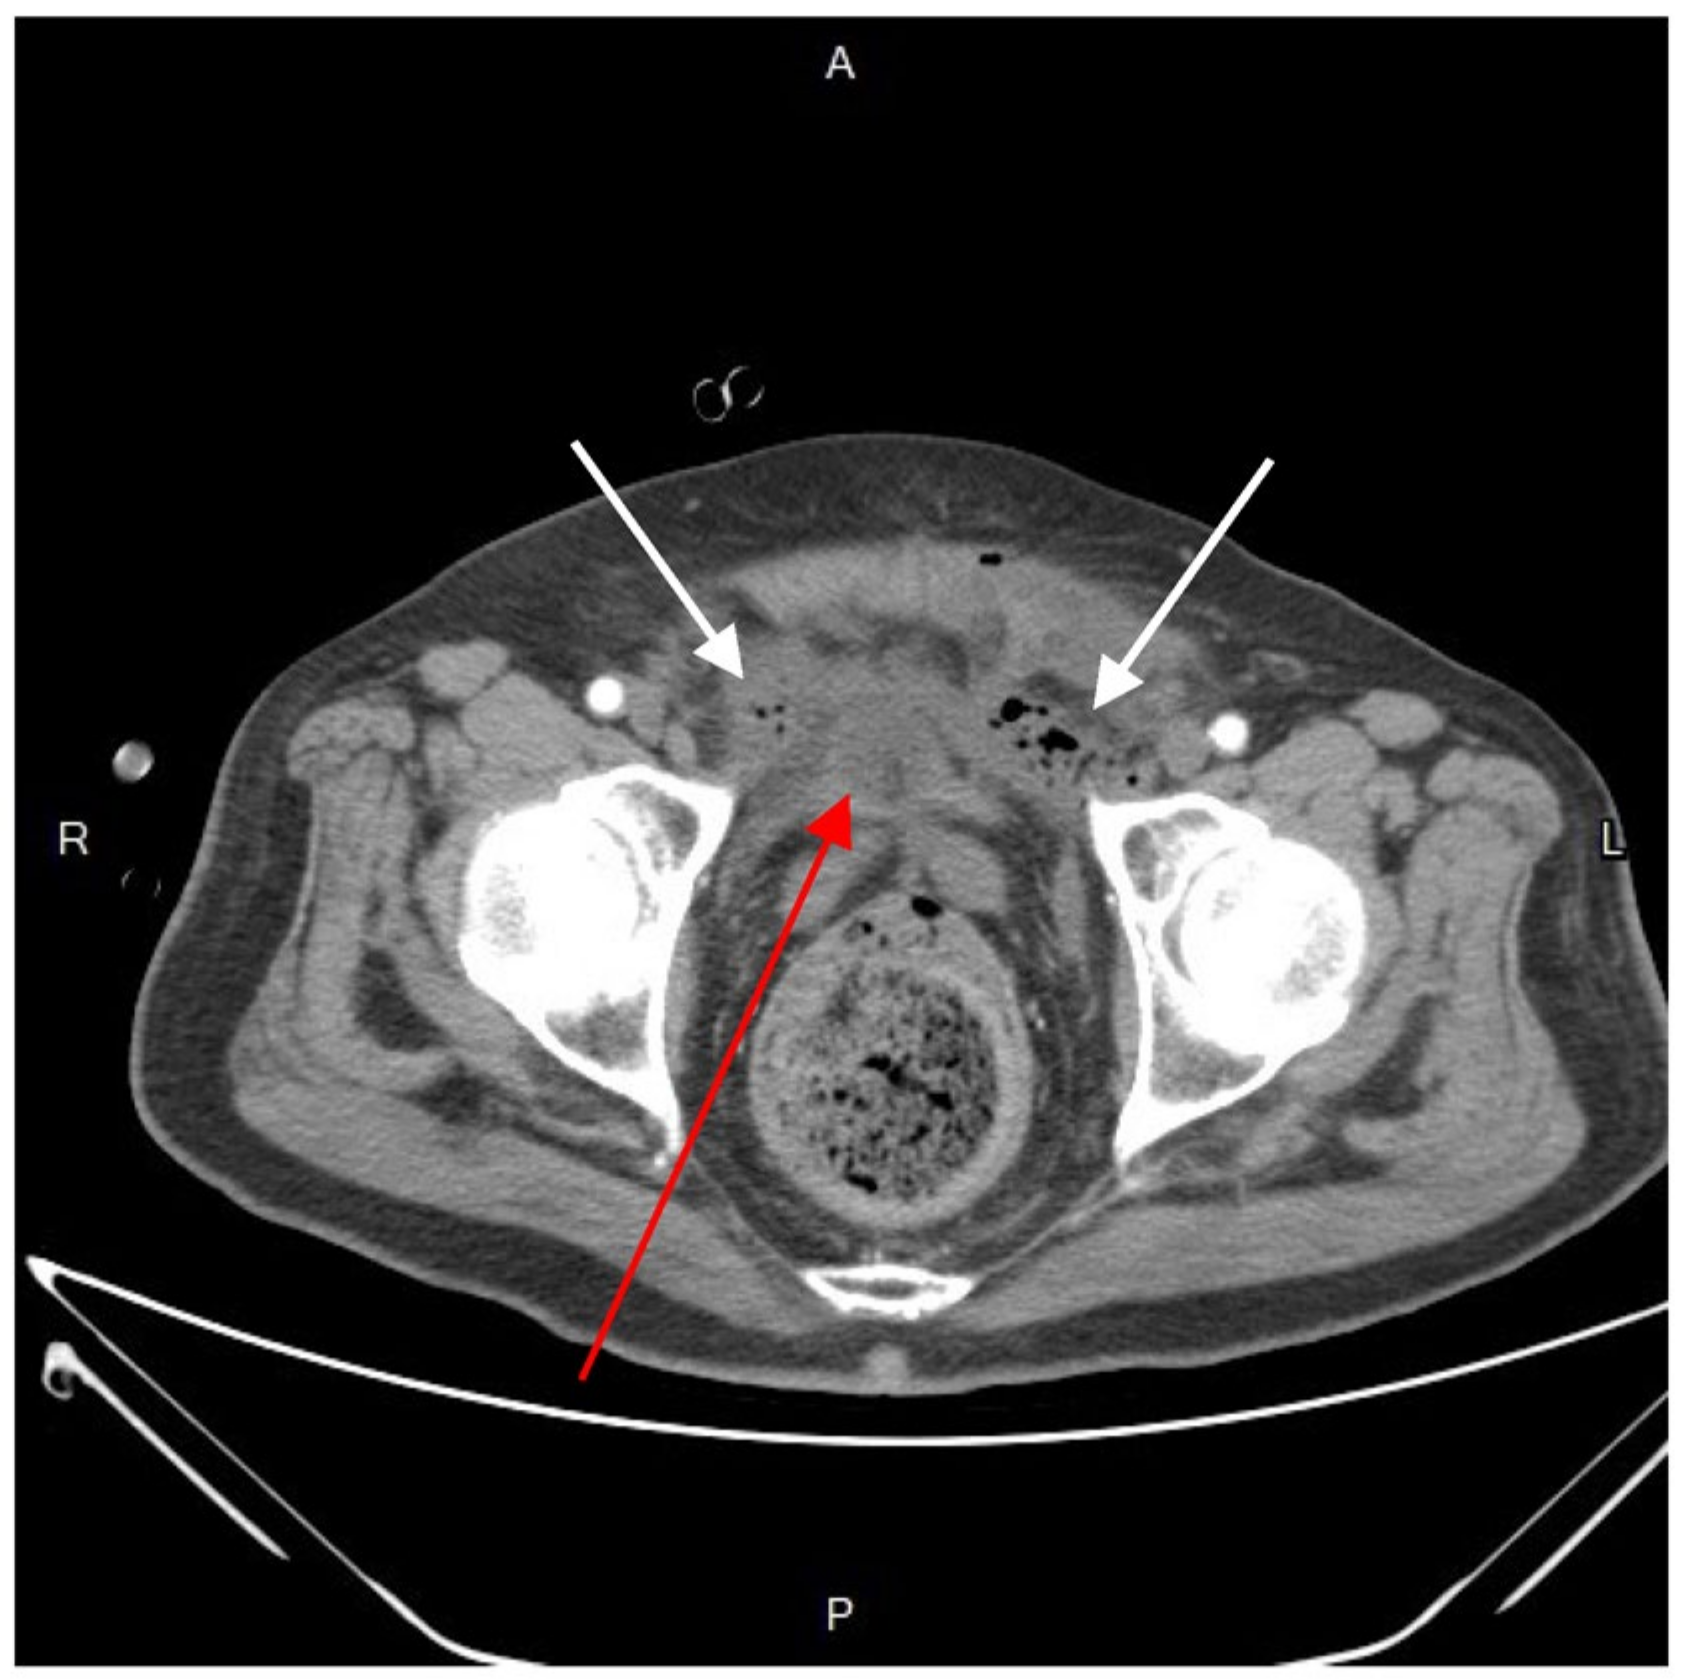

Blood cultures were drawn, and broad-spectrum empiric antibiotics (meropenem) were initiated. Following fluid resuscitation, the patient underwent incision and drainage in the 8 o’clock region. A cystic-like cavity filled with pus and surrounded with granuloma was found. We debrided and irrigated the lesion as much as possible and afterwards placed a Foley tube for adequate drainage and irrigation. Subsequent dressing changes were conducted regularly for proper hygiene. However, ten days after the surgery, the patient experienced sudden massive rectal bleeding, resulting in hypovolemic shock. Upon examination with an anal retractor, an oozing site with active bleeding was identified in the rectum in the 9 o’clock region. On the spot, the bleeding was managed by suturing ligation with 2-0 Vicryl successfully. Meanwhile, a colonoscopy revealed no obvious bleeding, mucosal constriction, fistula, rectal ulcers, or pre-malignant abnormalities. Simultaneously, an emergent abdomen and pelvic CT scan indicated no contrast medium extravasation in the bowel lumen or peritoneal space. Still, it identified an irregularly thick wall at the right side of the rectum (1.85 × 5.9 cm) and an extraperitoneal abscess around the bladder. Despite these findings, an anal-rectal fistula was not observed based on image surveys and physical examinations.

After resuscitation and blood transfusion, the patient’s vital signs stabilized, and the inotrope support was tapered. The next day, as confirmed by the CT scan and concerned about the further progression of infection, we consulted a radiologist for CT-guided extraperitoneal abscess drainage (Figure 4) and collected a significant amount of turbid fluid. Cultures from the pus were used to identify Klebsiella pneumoniae, Escherichia coli, Viridans streptococcus gr., and Bacteroides fragilis. Subsequently, antibiotic treatment with piperacillin-tazobactam was prescribed accordingly.

Figure 2. Axial view of contrast-enhanced computed tomography. An emphysematous collection of fluid-and-air-filled cavity (white arrow) in the perivesical space, dominantly on the left side. A Foley catheter with inflated balloon was dwelled in the bladder (red arrow). R, right; L, left; A, anterior; P, posterior.